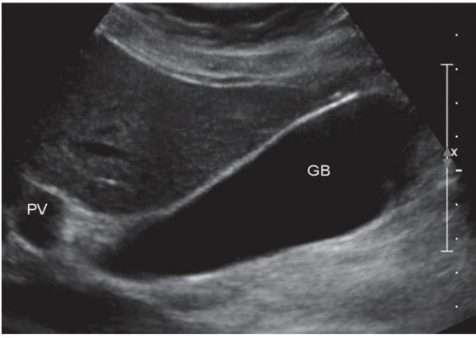

What view of GB?

Long, Portal Vein on the Left and Liver